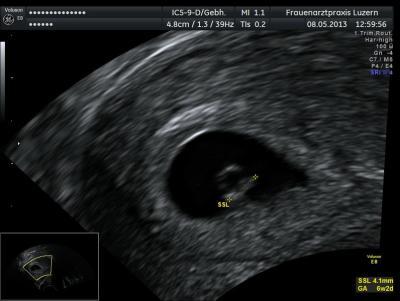

Hallo zusammen ich hatte vor einer Woche meinen 2. Termin beim FA, beim ersten Termin sah es ja nicht so gut aus das HCG recht tief war, ich ging also mit etwas Angst zum 2. Termin, und siehe da der FA war überraschter als ich, Herz hat schon gebubbert, Krümmelchen 3.5 mm gross soll zeitgerchet entwickelt sein für ca 6+2 - 6+4, ET soll der 28.12.2013 sein Jetzt soll ich aber erst am 19.06 wieder zum ersten Sreening vorbeikommen, ist das nicht extrem lang? In dieser Zeit kann ja weiss ich nicht was passieren, oder ist das normal? Ich hab nicht viele Beschwerden ausser Müdigkeit und nächtliche Gänge zum Klo, daher kann ich mich so gar nicht an was festhalten.... Wie ist das bei Euren Frauenärzten?

Bild zu Erst in 5 Wochen den nächsten Termin ist das normal? - Forum für Dezember - Mamis